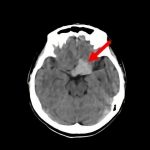

断層撮影

手術前2